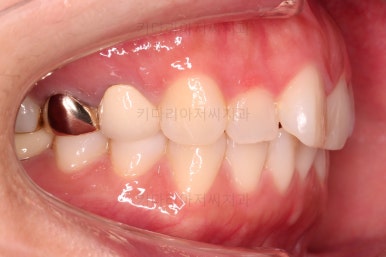

어금니의 맞물린은 100점은 아니지만 생활하기에 크게 나빠보이지 않고요.

특히 임플란트도 있는 상황이었기 때문에 굳이 어금니까지 교정할 필요는 없어보였어요.

이번에 부산부분치아교정 환자분이 선택하신 장치는 엠파워 클리어라고 하는 자가결찰 세라믹인데요.

흔히들 아시는 클리피씨가 이러한 종류의 장치에요.

아랫니는 일반 브라켓 보다 매우 작은 장치가 들어갔는데요.

미니튜브 장치에요.

일반적으로 MTA 장치라고 많이 알려져 있는데요. MTA라는 상품명과는 다른 장치이긴한데 왜 이 장치를 사용했을까요?

보기도 덜 보이는 장점이 있지만 이번 환자분의 경우에는 아랫니가 약간 솟구쳐 오르면서 장치를 부착하게 되면 씹혀서 매우 불편감이 예상되었었어요.

그래서 초기 정렬단계에서는 미니튜브를 이용해 주고, 추후에 좀 더 정교한 조절이 필요한 상황에서는 브라켓장치(엠파워 클리어)로 재부착하기로 했어요.

그리고 아랫니 송고니 옆 잇몸에 보시면 미니스크류가 식립이 되어있는데요.

이는 솟구친 아래 앞니의 높이를 조절하기 위해 사용이 됩니다.

이부분이 해결이 되어야 좀 더 완성도 높은 부분교정이 가능해요.